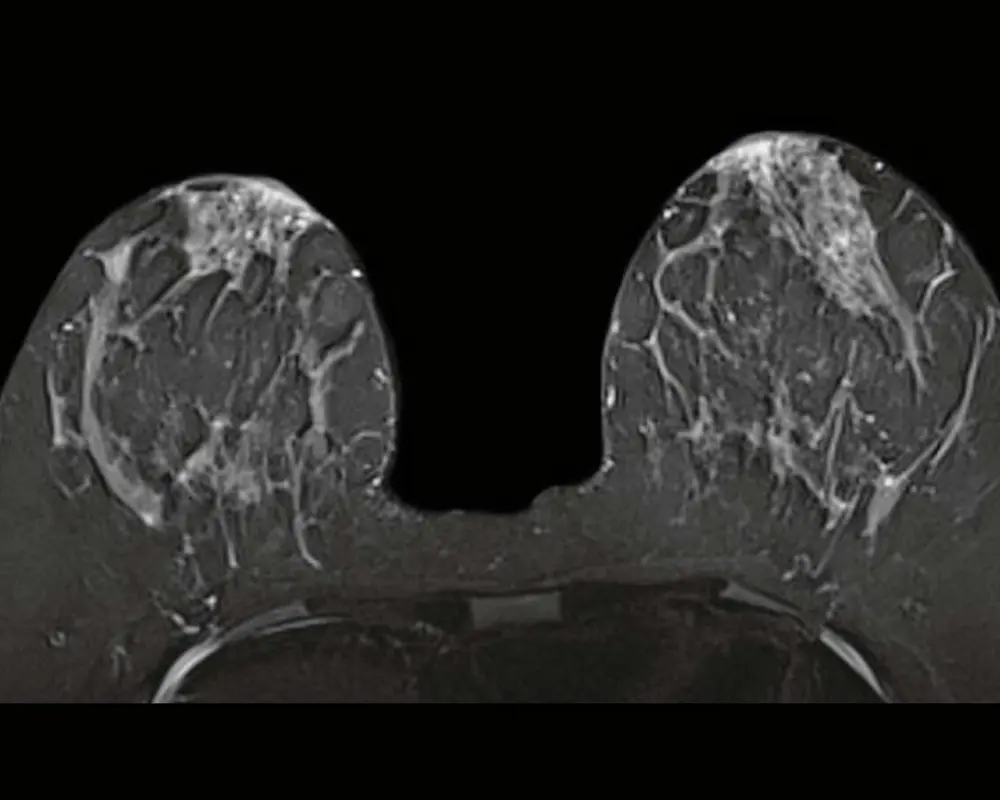

Breast MRI is a highly detailed imaging method used to examine breast tissue more closely than standard imaging. It is often recommended when additional clarity is needed, especially in cases involving dense breast tissue or areas that require further evaluation.

Breast MRI is often recommended when a more detailed view of breast tissue is needed beyond standard imaging. It provides deeper insight into areas that may not be clearly visible on a mammogram or ultrasound, especially when further evaluation is required.

At Maximum Resolution Imaging Center, our breast MRI in Houston TX and Richmond TX helps detect conditions such as breast lesions, abnormal tissue changes, implants evaluation concerns, and areas that may require closer examination. This advanced imaging supports early detection and helps guide the next steps in care with greater clarity and confidence.

Detailed Breast Imaging

Breast MRI provides highly detailed images of breast tissue, helping identify abnormalities that may not be visible through other imaging methods. It supports accurate diagnosis and better evaluation.

Accurate Breast MRI Imaging

During your breast MRI scan, high-resolution images are captured to evaluate breast tissue and detect abnormalities. This supports accurate diagnosis and helps guide better treatment and care decisions.